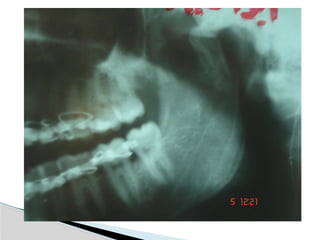

Conventional Radiology

At least 2 views at right angle to each other.

Mandibular series: PA, Lateral oblique or

panoramic, & Towne’s view (projects condyle

below mastoid process).

Conventional Radiology At least2 views at right angle to each other. Mandibular series: PA, Lateral oblique or panoramic, & Towne’s view (projects condyle below mastoid process). CT Significant displacement or dislocation, mechanical obstruction, mult trauma pt, & intracapsular fracture. MRI St injuries: effusion, visualization of disc. Imaging